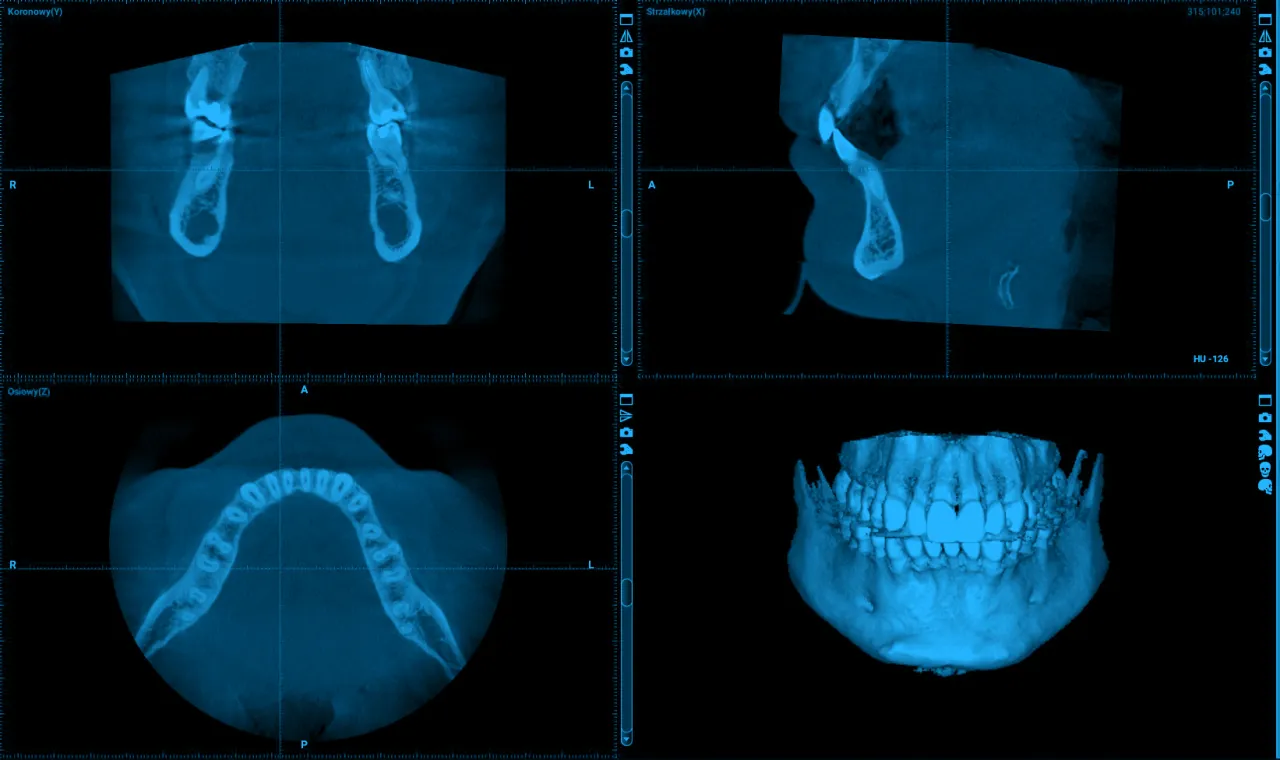

Tomografia komputerowa 3D (CBCT): W najtrudniejszych i najbardziej skomplikowanych przypadkach diagnostycznych, zwłaszcza przed zaawansowanym leczeniem kanałowym, implantologicznym czy chirurgicznym, tomografia wiązki stożkowej (CBCT) jest niezastąpiona. To najbardziej dokładne badanie obrazowe, które dostarcza trójwymiarowej oceny struktur zęba, kości i otaczających tkanek. Pozwala mi precyzyjnie zlokalizować dodatkowe kanały korzeniowe, ocenić stopień resorpcji kości czy zaplanować usunięcie trudnego zęba.